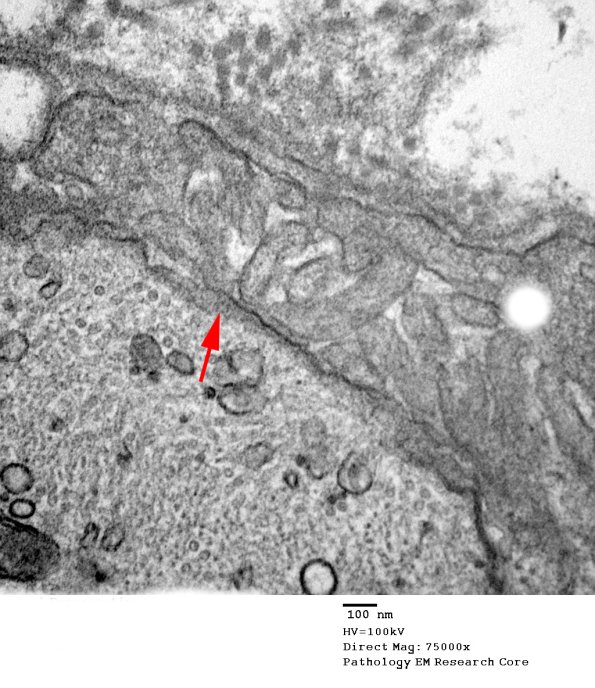

The sub-axolemmal density (arrow) contributes to the overall dense appearance of the axon. (electron micrograph)